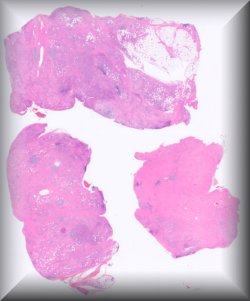

Alan D. Proia (Durham, North Carolina): Malignant mixed tumor of the eyelid. |